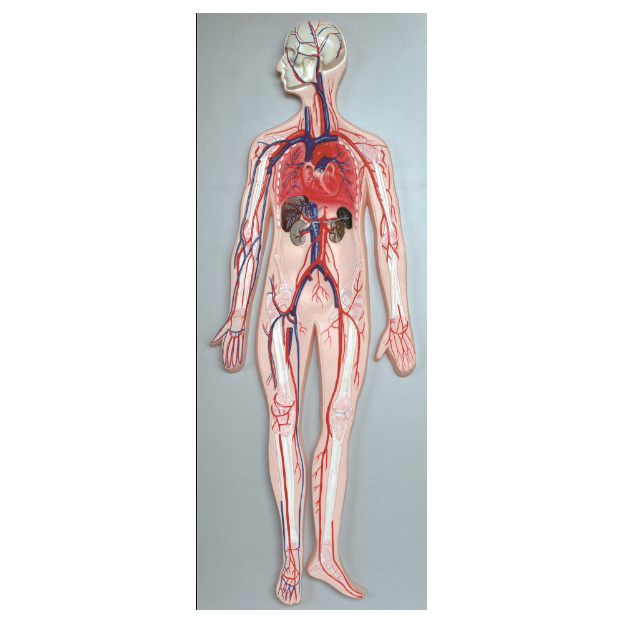

Анатомия человека: кровеносная система и её связь со скелетом